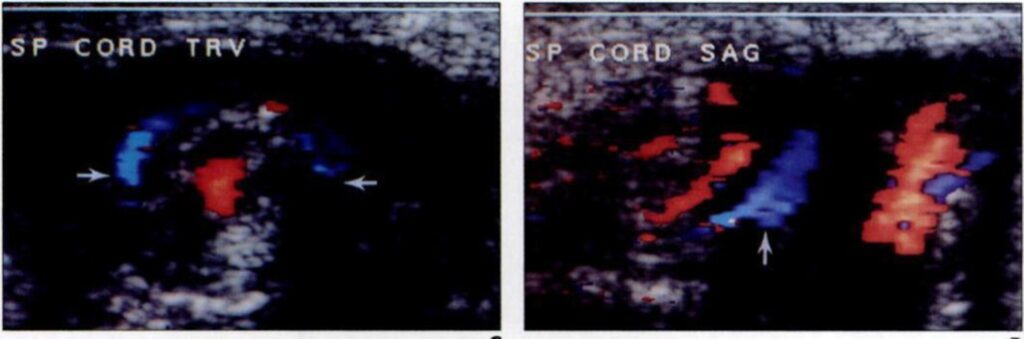

Pool Side: One of the most reliable indicators of torsion is the whirlpool sign, which represents the spiral twisting of the spermatic cord. Finding this sign above the testis (indicating at least a 360-degree twist) has been reported in the literature to have as much as 100% sensitivity and specificity for torsion.

- Check the Cord: Always perform longitudinal and transverse imaging of the spermatic cord vasculature—not just the testis, itself.

- “Boggy” Cord? In cases of intermittent torsion where a whirlpool isn’t obvious, an abnormal or thickened cord is a significant finding that supports the diagnosis.